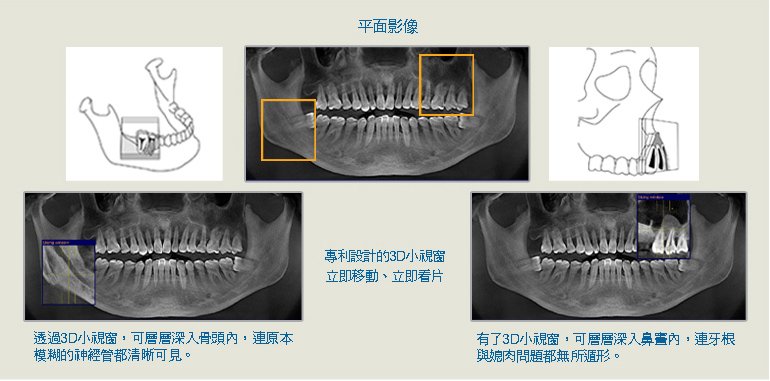

簡言之,透過電腦斷層,將可清楚瞭解患者的口內3D狀況、骨質密度、神經走向,以及與上顎鼻竇的距離,這是傳統平面X光所做不到的。本院所引進的「GALILEOS 3D」,拍攝時間僅需14秒。不但是植牙醫師植牙時的優越參考輔助,也能更清楚地向患者做手術方面的說明。為醫病雙方的權益,做更為妥善的把關。

●透過3D影像,可有效測量牙根與上顎鼻竇的正確距離,避免打穿。

主要的關鍵是,3D數位電腦斷層所建構而成的立體成像,比起傳統的平面X光片,在方位判讀上更為精準。臨床實務上,植牙手術很重要的是瞭解解患者齒槽骨內神經管的確切位置,及骨質密度是否可以接受植牙。

倘若植牙患者事先只有拍攝傳統的2D(平面)X光片,牙醫師將只能仰賴過去的經驗做判斷。也因此,傳統上經常發生醫生在進入到手術過程以後,才發現患者的條件並不適合植牙。

本院必須強調,在植牙手術前拍攝CT電腦斷層,可對骨頭狀況、神經管走勢、植牙位置做360度的確認,骨頭條件一覽無遺,提供診斷上的準確性,在提高手術成功率的同時,也可降低手術風險。健康,不可重來。尤其植牙手術所費不貲,花一樣的預算,為何不選擇具有CT電腦斷層的牙科診所呢?本院提供植牙患者3D電腦斷層拍攝服務,歡迎利用。